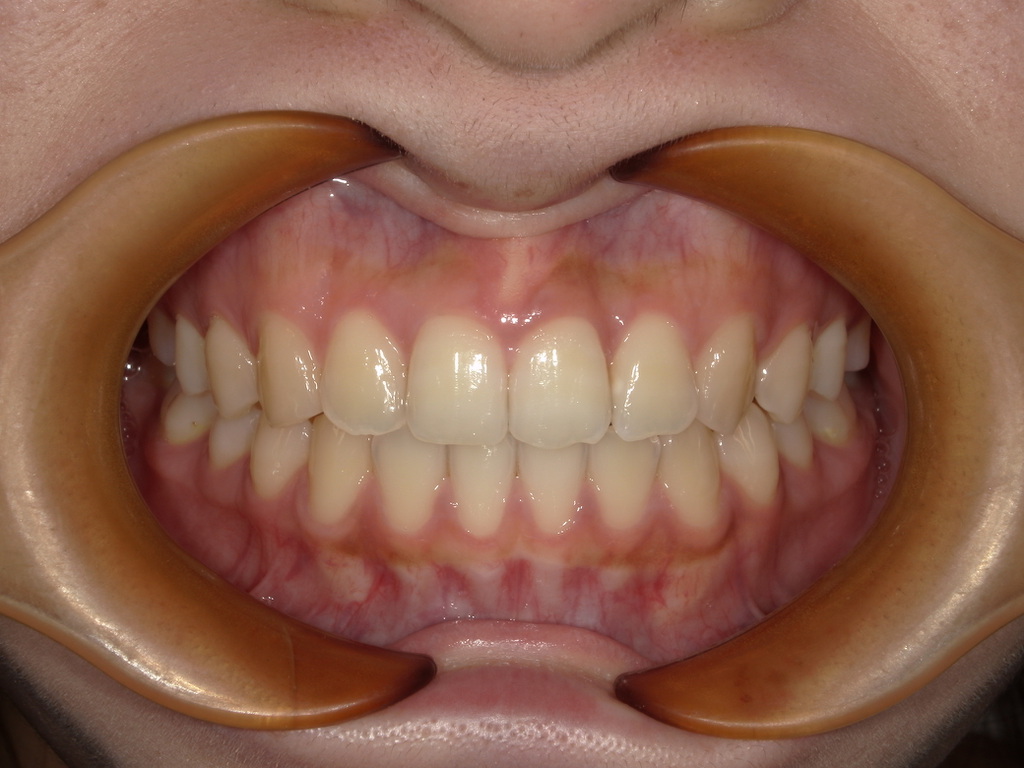

舌癖がある方の治療症例

最後に症例のご紹介をします。

患者様のご協力次第では治療期間も変わってきます。舌の位置の見直しをしましょう!!